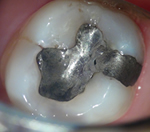

上のような小さな歯が、マイクロスコープではこのように見えています。

むし歯の治療(カリエス処置)

指の先ほどの歯の中の、むし歯の部分だけを除去しなければなりません。

むし歯の部分を取り損ねたら再発し、削り過ぎると歯を弱くしてしまうので、注意力と集中力が必要です。

マイクロスコープを用いれば視野を拡大して見られるため、健康な歯を痛めずむし歯の部分だけを除去できます。